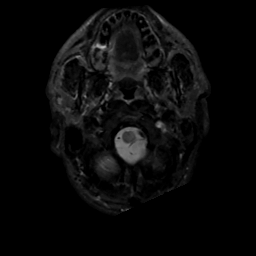

MR Study #3, February 24, 1991 -- Slice #2

[Home][Help][Clinical][Tour 1][Tour 2] Slice 2